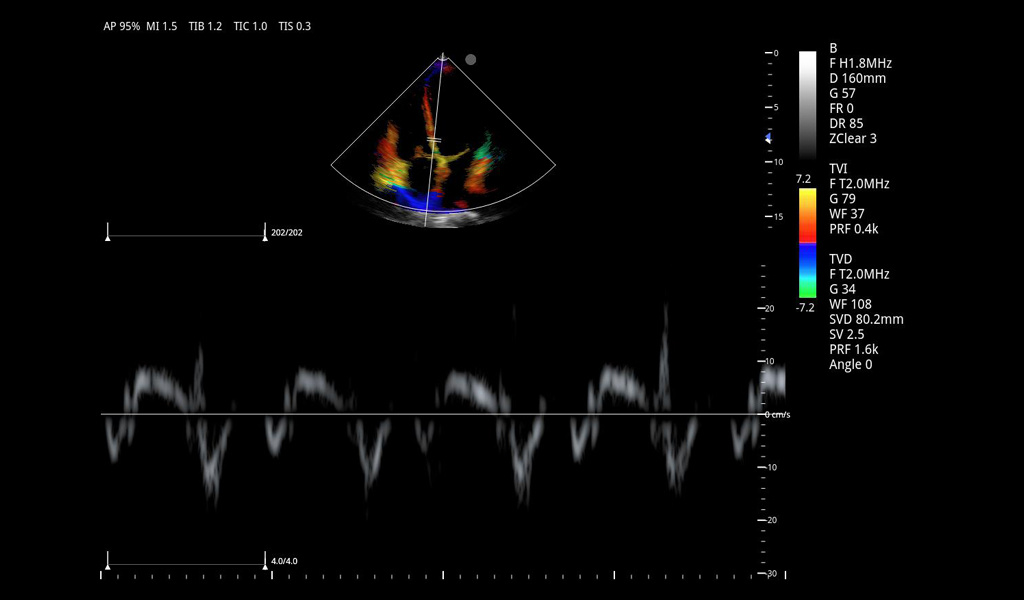

Excelentes imágenes clínicas

|

|

|

|

|

|